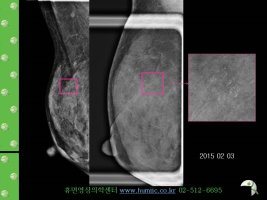

검사 결과로 많이 본 단어이지요?^^ 도움이 되셨으면 좋겠어요..^^ ※검진을 받았는데 유방이 석회화 되었다고 하는데 무슨 말인가요? '석회화'(calcification)란 유방 사진촬영에서 유방조직 내에